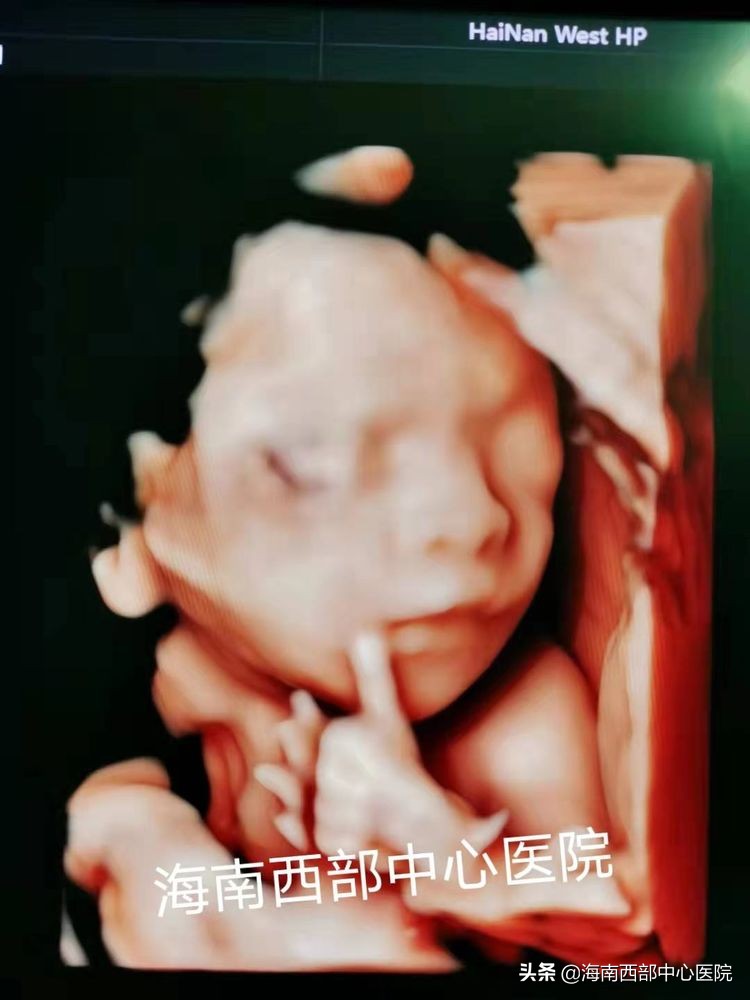

子宫输卵管超声造影是指向宫腔注入超声造影剂后,采用经阴道实时三维超声造影技术,实时观察宫腔及输卵管的显影状态,以判断子宫腔有无异常、输卵管腔是否通畅、输卵管走行有无盘曲等。